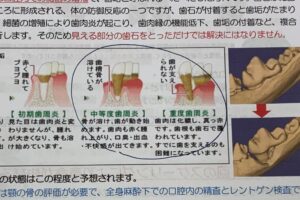

通常、人間の歯科医院では治療を始める前にレントゲンを撮影することが一般的です

犬や猫の口は、(食後を除いて)無臭であることが本来の状態とされています